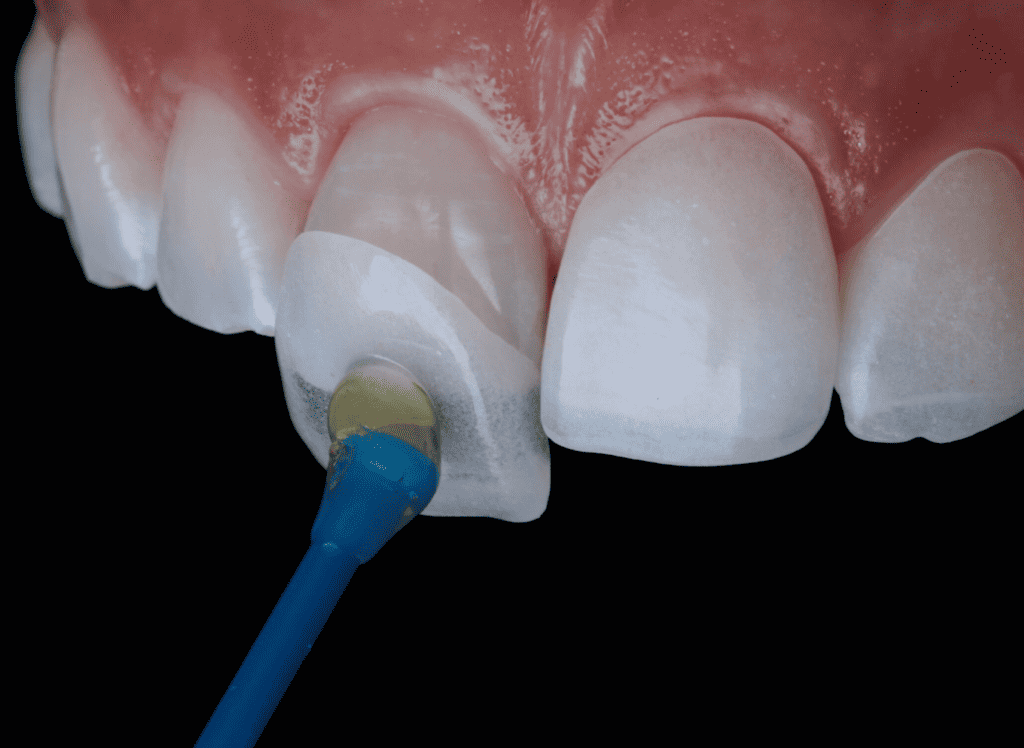

Se realizan directamente en clínica por nuestros odontólogos, aplicando capas de composite estético sobre el diente y moldeándolas hasta conseguir la forma deseada. Son una opción rápida y reversible.

Se diseñan en laboratorio para obtener una mayor precisión y resistencia. Se colocan sobre los dientes tras un análisis y planificación detallada. Son ideales para cambios más duraderos y con un acabado altamente estético.

✔ Preparación dentaria y toma de impresiones

✔ Colocación de carillas provisionales y pruebas estéticas

✔ Colocación final de las carillas dentales